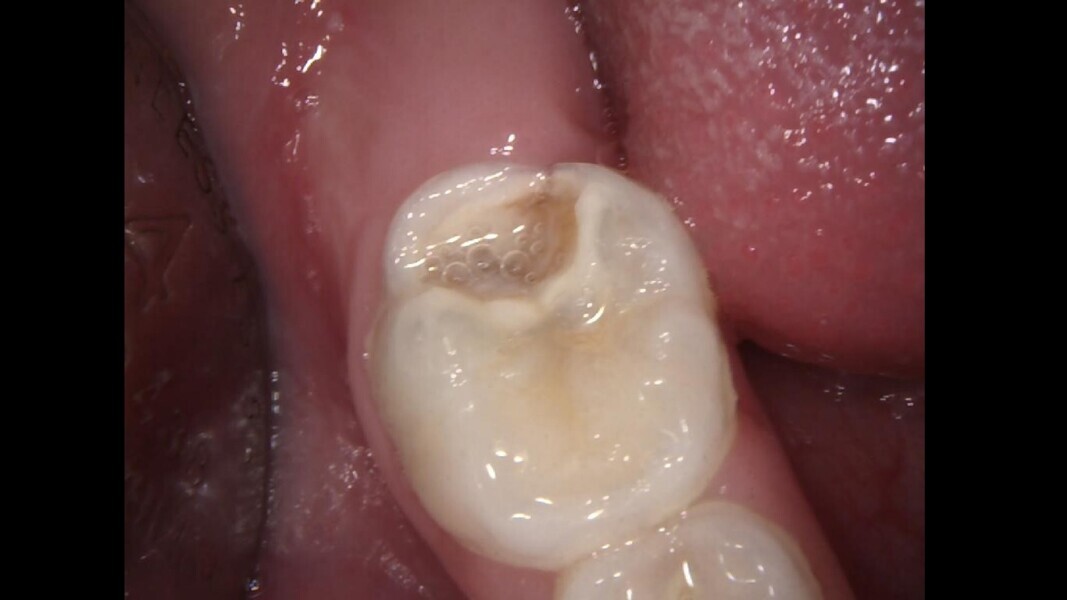

Case 4 (Figs. 14–18)

This male patient was 4 years and 6 months old and presented with constant and spontaneous pain of the mandibular left first primary molar that had lasted for several days but no facial oedema or buccal gingival swelling. Deep decay was observed but no mobility or deep probing depths. On the radiograph, the carious lesion could be seen to be compromising the pulp chamber and initial bone damage was observed in the septal area. Pulpectomy was the treatment of choice. In the removal of the carious lesion, the pulp was exposed and no bleeding was observed. Pulp necrosis was diagnosed. Two mesial and two distal canals were located, and the tooth was obturated. At a second appointment, the tooth was asymptomatic and was restored with a stainless-steel crown. At the 30-month control, the tooth presented no symptoms and a normal eruptive process was observed on the radiograph.